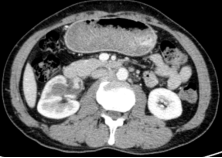

廣泛開展腹腔鏡下腎癌根治術(shù)、腎盂癌根治術(shù)、腎部分切除術(shù)、腎腫瘤剜除術(shù)、腎上腺腫瘤切除術(shù)、腎盂輸尿管成形術(shù)、腎囊腫去頂減壓術(shù)、輸尿管上段切開取石術(shù)等。全腔鏡下進(jìn)行,創(chuàng)傷小、恢復(fù)快。

腹腔鏡腎腫瘤剜除術(shù)(保腎) 腹腔鏡腎癌根治術(shù) 腹腔鏡腎盂癌根治術(shù)